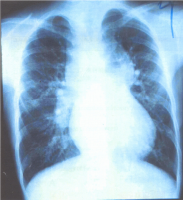

13. 一位 5 歲男孩,其父母主訴他運動時嘴唇發紺(cyanosis),且較正常人喘。於左胸前可聽到第 2-3 度 心雜音,其胸部 X 光檢查如圖所示。下列何者為最可能的診斷?

(A)總肺靜脈回流異常(total anomalous pulmonary venous return) (B)大血管轉位(transposition of great arteries) (C)三尖瓣膜閉鎖(tricuspid atresia) (D)法洛氏四合症(tetralogy of Fallot)